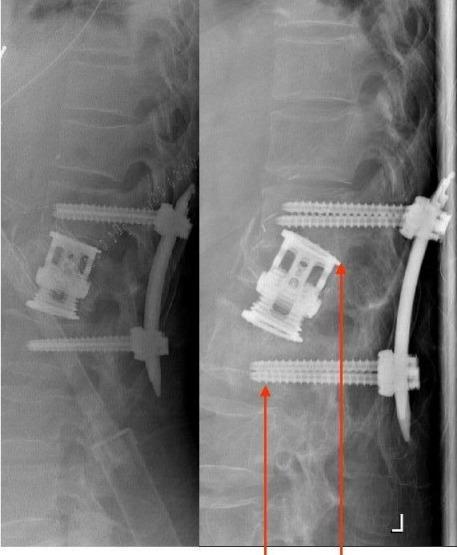

Specific and non-specific infections of the spine are rare. Due to their potential for severe instabilities, deformities and the impairment of neurological structures, the treatment is often prolonged and needs an interdisciplinary management. The clinical presentation is uncharacteristic, therefore diagnosis is often delayed. There are no prospective randomized studies for therapy recommendation. The surgical concept includes eradication of the infection and the reliable stabilization of involved segments. This concept is successful in most cases of endogenous vertebral osteomyelitis. The therapy of the exogenous spine infections after macro and micro surgery is more difficult, due to the critical wound situation and the involvement of the posterior parts of the spine. In these cases, infection-associated instability of the anterior part is complicated by critical posterior wound conditions. We present three cases of severe exogenous vertebral infections, where temporary external transpedicular spine fixation was used for salvage procedure, till soft tissue conditions have permitted a definitive internal stabilization.

脊柱的特异性和非特异性感染较为罕见。由于它们可能导致严重的不稳定、畸形以及神经结构受损,治疗往往较为漫长,且需要多学科管理。临床表现不典型,因此诊断常常延迟。目前尚无用于推荐治疗方法的前瞻性随机研究。手术理念包括根除感染以及对受累节段进行可靠的稳定固定。这一理念在大多数内源性椎体骨髓炎病例中取得了成功。由于伤口情况危急以及脊柱后部受累,宏观和微观手术后外源性脊柱感染的治疗更为困难。在这些病例中,前部感染相关的不稳定因后部伤口情况危急而变得复杂。我们展示了三例严重的外源性椎体感染病例,其中采用了临时经椎弓根外固定脊柱进行挽救手术,直至软组织条件允许进行最终的内固定。